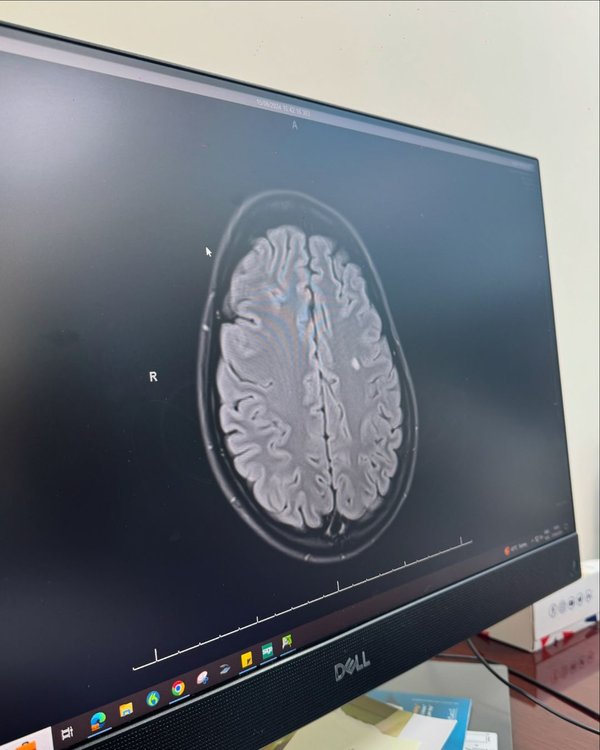

عانت نارين من تعب في جسدها، مما جعلها تخضع للعديد من الفحوصات والرنين المغناطيسي ليتبين أن لديها 3 نقط بيضاء على الدماغ بأحجام مختلفة.

" اليوم اخدت قرار اني شارك معكم جزء من حياتي بالفترة الأخيرة و سبب ظهوري القليل على السوشيال ميديا الي انتو مالكم متعودين عليه بس صدقوني احيانا الظروف بتكون اكبر مننا.من فترة تعبت صحتي و حسيت انه في شي غلط بجسمي ف رحت اعمل فحوصات عامة و ما كنا نعرف السبب للتعب الجسدي لبين ما قررنا نعمل رنين مغناطيسي للدماغ، و اكتشفنا انه كان في عندي ٣ نقط بيض على الدماغ بأحجام مختلفة و حاليا رح أخوض رحلة لمدة سنتين لحتا أتابع مع الدكتور لنتأكد انه ماله مرض مناعي و انشالله خير.